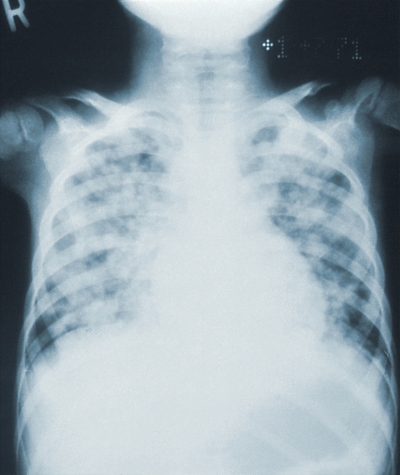

폐렴은 세균이나 바이러스에 의해 폐의 세기관지 이하 부위, 특히 폐포라 불리는 공기주머니에 발생한 염증을 말합니다. 폐의 정상적인 기능에 장애가 생겨서 발생하는 폐증상과 몸 전체에 걸친 전신적인 증상이 나타납니다.

과거에는 폐렴에 걸리면 죽음으로 가는 지름길이라고 말할 정도로 사망률이 높았다고 합니다. 폐렴으로 인한 사망자는 꾸준히 증가하고 있으며 특히 노인 사망에 미치는 영향이 크다고 합니다.